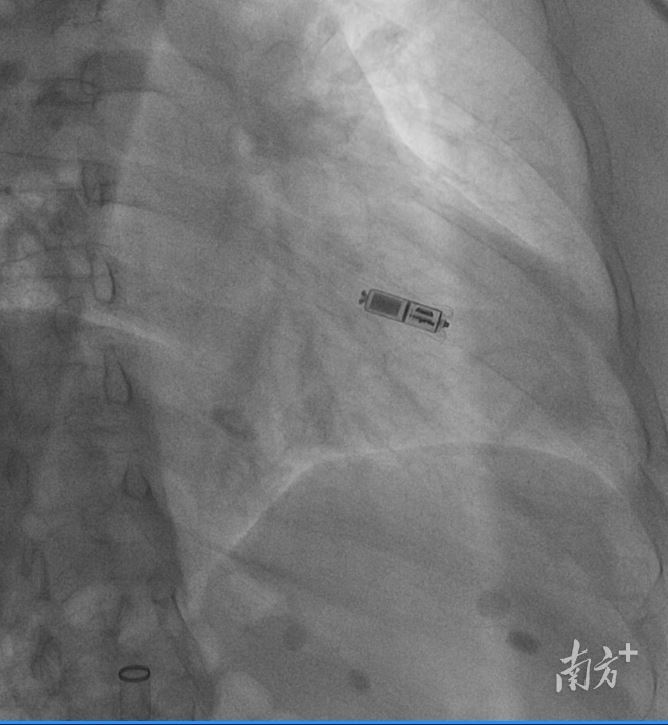

无导线起搏器成功植入心脏内。

无导线起搏器,顾名思义,就是没有导线,将脉冲发生器与起搏电极合为一体,以“微缩胶囊”的形式直接将起搏器植入患者心腔内部。体积仅有胶囊大小,体积比传统心脏起搏器减少93%,重量仅约2克。

重量仅2克的新一代无导线起搏器。